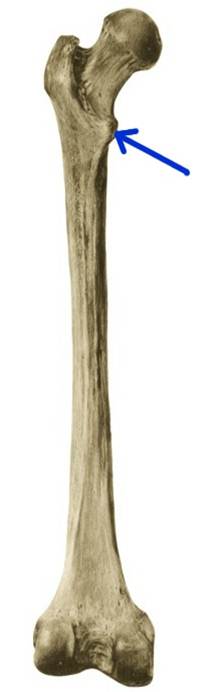

S: Стрелка указывает на caput femoris

S: Стрелка указывает на trochanter major

S: Стрелка указывает на collum osis femoris (латинский язык).

S: Стрелка указывает на linea intertrochanterica

S: Стрелка указывает на crista intertrochanterica